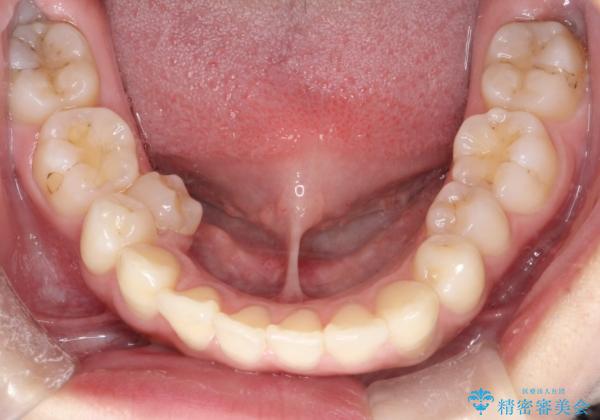

右下第二小臼歯の舌側転移の改善

- 患者様は、右下第二小臼歯が舌側に転移していることが主訴でした。診断の結果、抜歯を伴う矯正治療も検討しましたが、奥歯の遠心移動とIPR(インタープロキシマルリダクション)を行うことで、非抜歯で矯正を進めることが可能であると判断しました。治療計画では、審美ワイヤーを用いた2年間の治療で、歯列を整えつつ、臼歯関係や正中のバランスを維持しながら進めました。

非抜歯矯正では、歯の動きを慎重に調整することが求められます。本症例では、奥歯を遠心に移動させることで、舌側に転移した右下第二小臼歯の位置を改善しました。また、IPRを行うことで歯間スペースを確保し、無理なく歯列の調整を行いました。非抜歯での治療は、特に臼歯関係や正中を保ちながら治療できるというメリットがあり、最終的にはバランスの取れた歯並びを実現できました。審美ワイヤーを使用したことで、治療中も目立ちにくく、患者様の見た目にも配慮した治療を行いました。